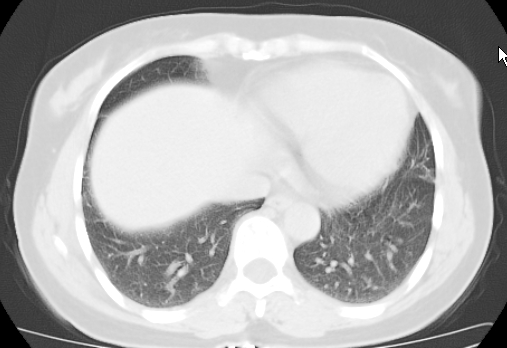

标题: CT25227:背部疼痛伴双侧胸壁痛2月,食欲差。 [打印本页]

标题: CT25227:背部疼痛伴双侧胸壁痛2月,食欲差。

肺结核并胸椎结核?请各位高手指教。

用椎体的条件来扫胸椎呀!考虑1左侧胸膜小结节形成2椎体结核并冷脓肿形成

考虑胸椎结核并椎旁软组织肿胀。

左肺结核灶,胸椎结核并冷脓肿。

支持!不排除骨原发淋巴瘤肺内转移。